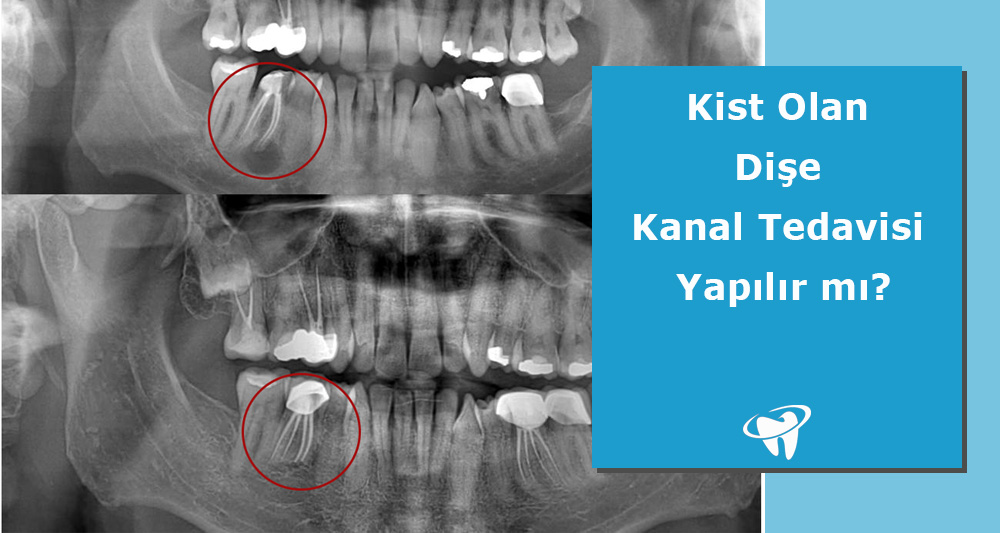

Kök ucu rezeksiyonu (endodontik cerrahi), kanal tedavisi ile tedavi edilmeye çalışılmış ancak çeşitli nedenlerle başarılı olunamamış vakalarda uygulanan bir yöntemdir. Kök ucunda enfeksiyonu bulunan ve kök kanalı vasıtasıyla enfekte bölgeye ulaşılması mümkün olamayan durumlarda tercih edilmektedir.